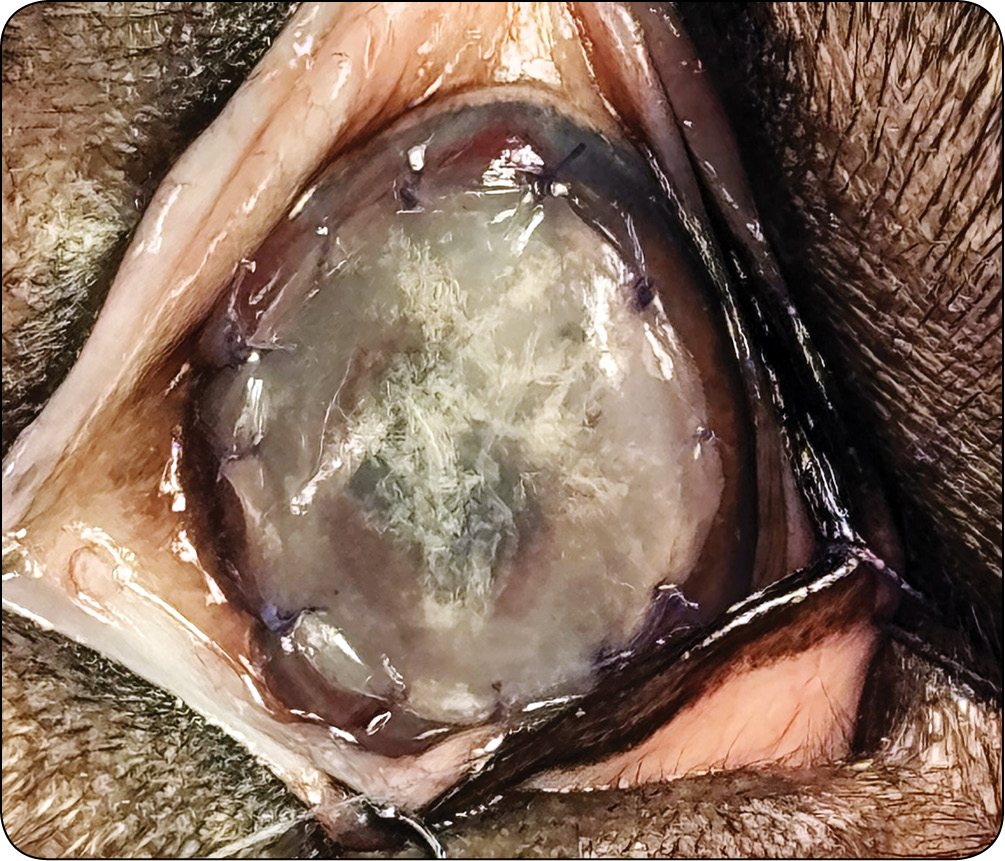

Owrzodzenia rogówki u małych zwierząt – klasyfikacja, diagnostyka i leczenie

Leczenie wspomagające